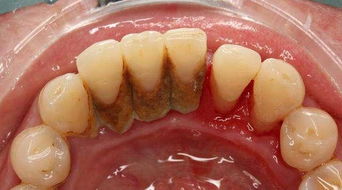

牙科醫生一般建議每半年洗一次牙結石,這樣可以減輕牙齦炎、牙周炎的炎癥狀況,但靠單純洗牙是不能治愈牙周病的。要治好牙周病,還應該在洗牙之后進(jìn)行進(jìn)一步的診斷和口腔專(zhuān)業(yè)的治療。

牙結石較厚,宜分次潔牙:牙結石較多較厚、藥物抗炎效果欠佳或脫敏醫治欠佳者,建議分次潔牙。

定期潔牙:常年累積的牙結石又多又硬,致使潔牙時(shí)需加大潔牙機的強度才能去除,這樣會(huì )加重牙齒酸痛感。因此建議大家定期到醫院潔牙,剛構成的牙結石量不多,質(zhì)較松,易去除,不易形成潔牙時(shí)的酸痛感。